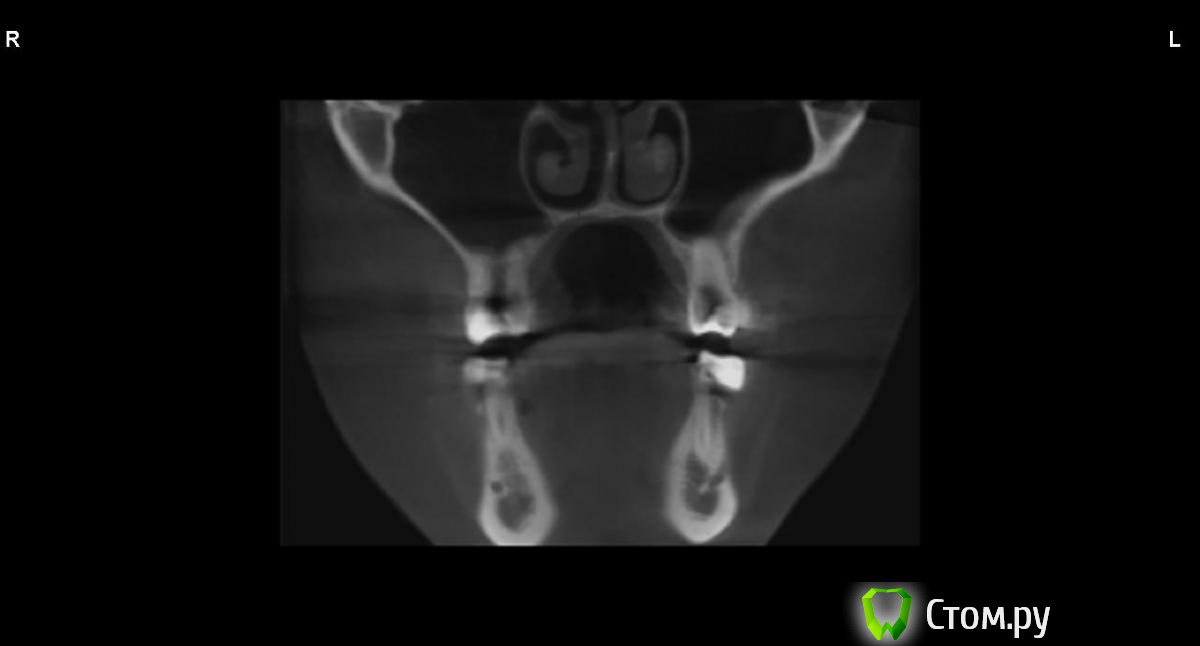

jm3300 Опубликовано 9 сентября, 2014 Автор Поделиться Опубликовано 9 сентября, 2014 вот, набросал Ссылка на комментарий

АнтонТЛТ Опубликовано 9 сентября, 2014 Поделиться Опубликовано 9 сентября, 2014 (изменено) это нижняя носовая раковина, возможно Изменено 9 сентября, 2014 пользователем АнтонТЛТ Ссылка на комментарий

АнтонТЛТ Опубликовано 9 сентября, 2014 Поделиться Опубликовано 9 сентября, 2014 я понял что это)))это артефакт от зуба, обратите внимание на правую сторону, там в пазухе тоже зуб есть, после эндодонтии)) Ссылка на комментарий